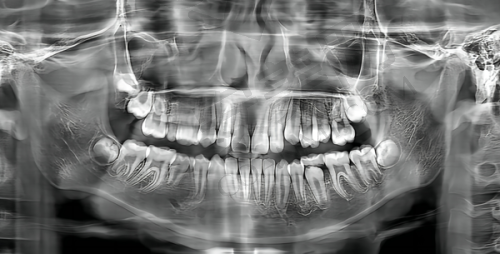

精良的设备:作为深圳市少有的二级口腔专科医院,新浩口腔在硬件配置上处于领跑地位。医院设有6层独立诊疗空间,包含多间无菌手术室和独立诊室,确保了诊疗的私密性。设备方面,引进口腔CT、数字化全景机、激光治疗仪等高端仪器,可获取三维影像数据,为复杂病例提供科学依据。正畸患者可通过3D扫描仪即时查看矫正模拟,种植手术采用动态导航系统实现微创操作,这些设备不仅提升了治疗的精细度,还缩短了患者的就诊时间。